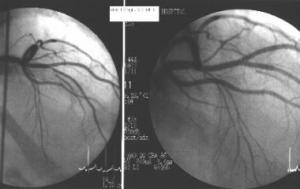

Coronary artery atherosclerosis is the single largest killer of men and women in the United States.